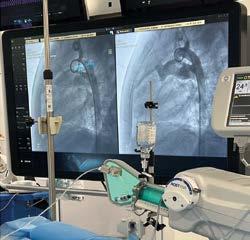

Inicia IMSS en Baja California cateterismos cardíacos pediátricos

Por primera vez, especialistas del Hospital General Regional (HGR) No. 30 y del Hospital de Gineco Pediatría (HGP) No. 31, en Mexicali, realizaron procedimientos de cateterismo cardíaco en niñas y niños, lo que representa un importante avance para la salud de la derechohabiencia pediátrica de Baja California y San Luis Río Colorado, Sonora.

Hasta ahora, más de 24 pacientes, de entre 1 y 13 años, han sido beneficiados. Estas intervenciones de alta especialidad son efectuadas por pediatras, cardiólogos clínicos, intervencionistas y ecocardiografistas.

El IMSS en el estado refrenda su compromiso de llevar atención de calidad a las niñas, niños y adolescentes.